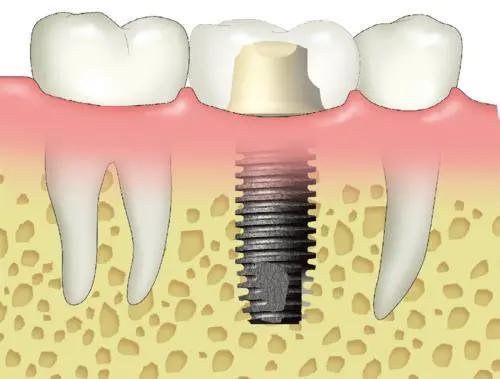

0mmx10mm植体_正畸_发炎_种植牙

种植牙示意图

种植牙结构图

种植牙图解